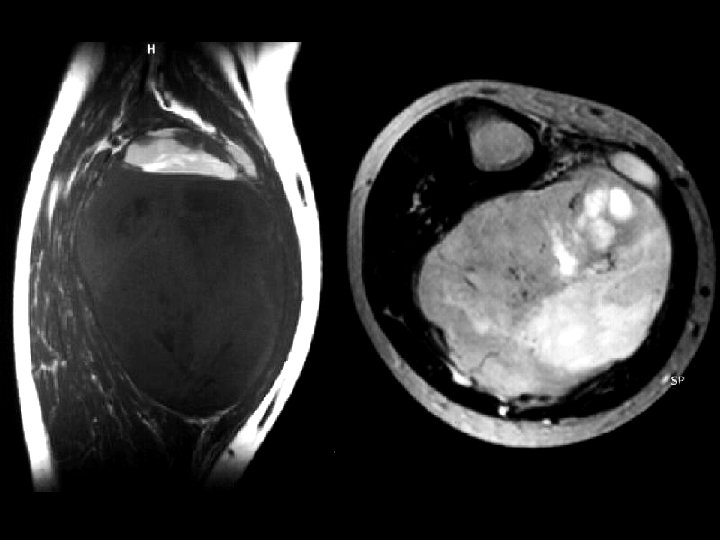

Aneurysmal bone cyst • Findings: – Lucent end of bone lesion in the proximal tibia – Slightly expansile, mild periosteal reaction – Fluid-fluid level on MRI • ddx: – Giant cell tumor – Unicameral bone cyst – Fibrous dysplasia – Chondroblastoma (rare)